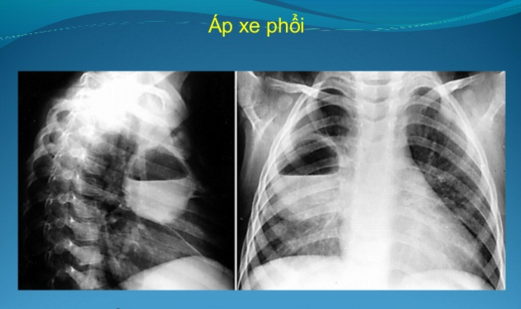

Áp xe phổi Định nghĩa: Áp xe phổi là bệnh viêm nhiễm cấp tính, gây nên hoại tử nhu mô phổi, tạo ra 1 hang có chứa mủ bên trong, mà nguyên nhân không phải do lao Các trường hợp kén khí, giãn phế quản, hang lao, hang ung thư nhiễm khuẩn không được coi […]